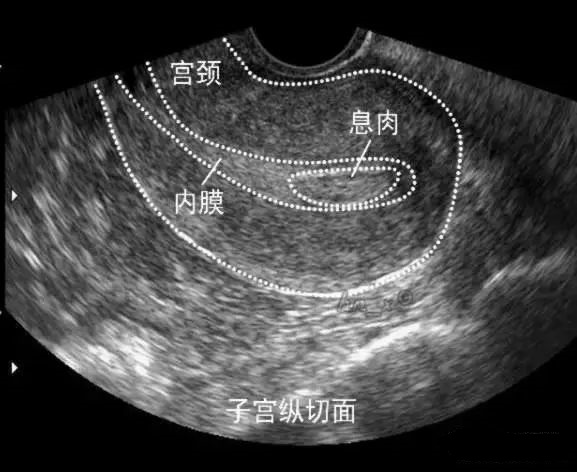

比如女生主要表现为子宫出血、绝经后不规则出血、不孕,也可表现为周期缩短、经期延长等。如果B超检查发现宫腔内见不均匀低回声或稍高回声周边高回声,与子宫壁边界清楚,形状呈椭圆形, 内部可见大小不一的等透声区;子宫内膜与息肉相连的纤维蒂清晰,子宫内膜弧线偏移; 可见子宫内少量积液,彩色多普勒超声检查显示部分息肉内部可见星点状或条状血流信号。

这个时候,我们就会下“子宫内膜息肉”的诊断。当然子宫里面的到底是不是息肉?还需要医生做宫腔镜检查,手术切除送病理,病理诊断才是金标准。